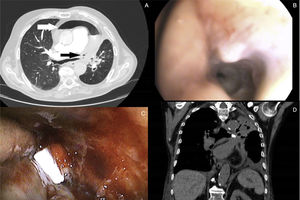

Our patient was a 71-year-old man, former smoker with a cumulative smoking index of 80 pack-years, diagnosed with T4N2M1 squamous cell carcinoma of the lung 2 years previously, receiving chemotherapy and radiation therapy. He attended the emergency room with a 48-h history of asthenia, and hypotension was detected. Computed tomography showed tension pneumopericardium (Fig. 1A) and bronchoscopy revealed a fistula orifice of about 5mm in the distal third of the left main bronchus which was constricted by the tumor (Fig. 1B). We decided to close the fistula by implanting a 6mm Watanabe spigot to occlude the fistula orifice and surround it with Bioglue® biological sealant (Fig. 1C). A follow-up computed tomography scan was performed at 48h, and the spigot was seen to be in the correct position (Fig. 1D). The patient progressed well, but despite this, he died a week later due to massive hemoptysis. Bronchopericardial fistula causing pneumopericardium is a rare and often lethal complication of lung carcinoma. Surgical treatment of bronchopericardial fistula is often unsuccessful due to anatomical limitations and intra-operative hemodynamic instability. Endoscopic management has rarely been used. We found no literature describing the implantation of a spigot in this indication, and very few other alternative treatment options are available.1,2

(A) Axial CT scan of the chest showing the path of the bronchopericardial fistula (black arrow) and pneumopericardium (white arrow). (B) Endoscopic image showing the fistula trajectory. (C) Endoscopic view where Watanabe spigot can be seen at the beginning of the fistula trajectory. (D) Coronal CT slice after 48h showing correct positioning of the spigot (arrow).